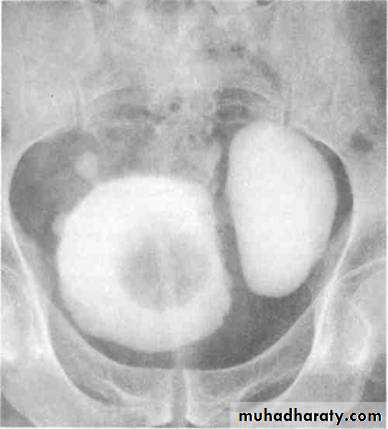

Benign Prostatic Hypertrophy. A radiograph from an excretory urogram shows marked uplifting of the bladder base because of massive enlargement of the prostate (P). The trigone (open arrow) and ureteral orifices (black arrows) are markedly elevated, resulting in a J-shaped appearance to the distal ureters (u). The bladder wall is thickened (between black arrowheads), and the bladder (B) mucosal pattern is prominent.